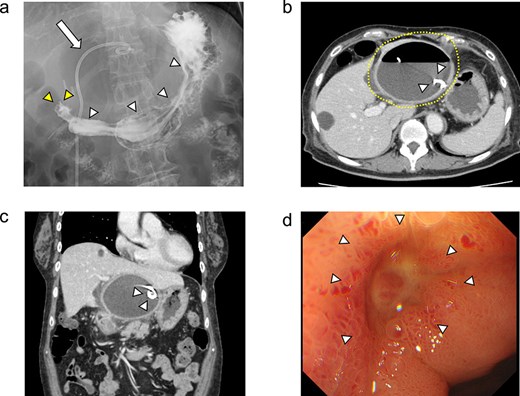

(a) Enhanced CT images findings obtained in the examination by the patient’s primary care physician. A 16-cm hepatic cyst in the left hepatic lobe area was observed. Dotted line: The hepatic cyst. (b, c) Plain CT images findings obtained at the patient’s hospitalization. (b) This axial section shows the large hepatic cyst in left hepatic lobe area, which was collapsed and contained air bubbles. There were no findings of free air or leakage into the peritoneal cavity. Arrowheads: The air bubbles of collapsed large hepatic cyst. (c) A low-density area between the hepatic cyst and the duodenum with a suspicion of a fistulous tract can be seen on this coronal section. Arrows: The low-density area between the hepatic cyst and the duodenum. (d) An abdominal X-ray finding after the percutaneous catheter aspiration of the hepatic cyst with a 7Fr pig-tail catheter (left arrow). Right arrow: The nasogastric tube.

She exacerbated her upper abdominal pain and was transferred to our hospital. The laboratory workup (Supplementary Figs S1 and S2) showed that her white blood cell count and CRP level were high at 13 300/μl (92.5% neutrophil count) and 41.72 mg/dl, respectively. CT revealed a large hepatic cyst in the left hepatic lobe that was collapsed and contained air bubbles. There were no findings of free air or leakage into the peritoneal cavity (Fig. 1b). The CT also identified a low-density area between the hepatic cyst and the duodenum; a fistulous tract between them was suspected (Fig. 1c).

She was started on antibiotic therapy, and the hepatic cyst was punctured percutaneously with a 7Fr pig-tail catheter (Fig. 1d), and the elevated inflammatory response in blood tests gradually improved.

On day 13 of admission, an upper gastrointestinal contrast examination showed no obvious communication between the hepatic cyst and the duodenum (Fig. 2a). On day 20, CT showed that the hepatic cyst had tended to shrink but had not disappeared; in addition, the cyst wall had thickened (Fig. 2b). The CT also identified a low-density area between the hepatic cyst and the duodenum, which we suspected was a fistulous tract between them (Fig. 2c). On day 21, an upper gastrointestinal endoscopy revealed an ulcer scar at the anterior aspect of the duodenum bulb (Fig. 2d). A biopsy of the ulcer scar tissue revealed no malignancy.

The upper gastrointestinal contrast examination findings on day 13 of the patient’s hospital admission. (a) There was no obvious fistulous tract between the hepatic cyst and the duodenum. arrowheads: The stomach, arrowheads: The duodenum. arrow: The 7Fr pig-tail catheter. (b, c) Enhanced CT images findings on 20 day of admission. (b) Axial section. A shrunken hepatic cyst with a thickened cyst wall was observed. Dotted line: The large hepatic cyst. Arrowheads: The 7Fr pig-tail catheter. (c) Coronal section. A a low-density area was observed between the hepatic cyst and the duodenum, suspected of being a fistulous tract. Arrows: The low-density area between the hepatic cyst and the duodenum. Arrowheads: The 7Fr pig-tail catheter. (d) An upper gastrointestinal endoscopy on admission day 21 showed an ulcer scar at the anterior aspect of the duodenum bulb without obvious fistulous orifice. Arrowheads: The ulcer scar at the anterior aspect of the duodenum bulb.